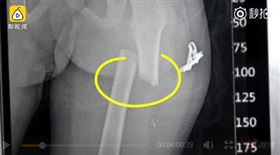

不爽6歲童走太慢 狠父竟踹斷他大腿

中國大陸一名狠父不滿6歲兒走路慢,竟一腳踹斷他的大腿...